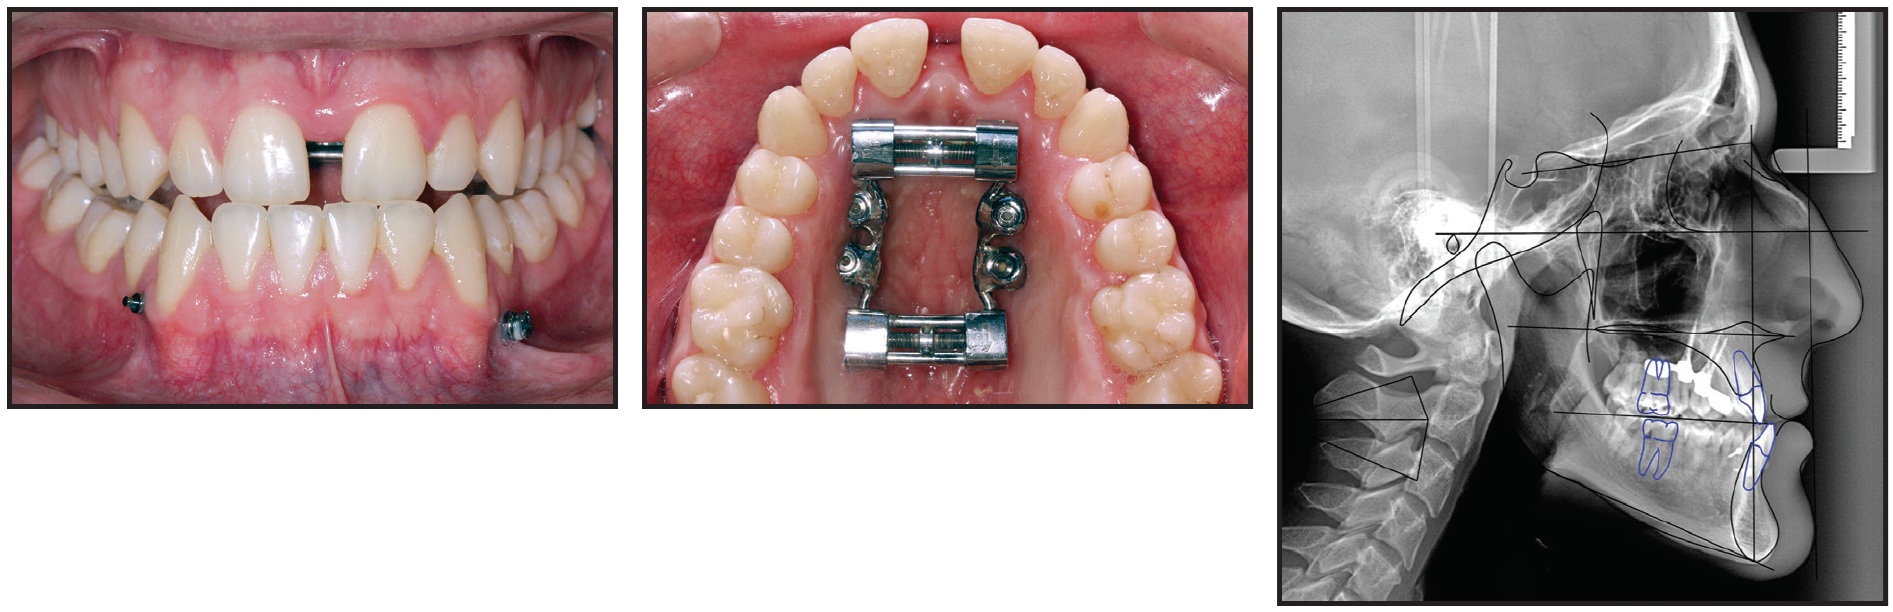

Four miniscrews (2mm in diameter) were inserted in the palatal vault: two 15mm miniscrews in the front, one 13mm miniscrew in the posterior right side, and one 15mm miniscrew in the posterior left side (Fig. 13). A TSE was placed, and the patient was instructed to perform two activations per day. The palatal expansion was completed after 21 days, when a diastema had developed between the central incisors as a result of opening the midpalatal suture (Fig. 14).

Fig. 13 Case 2. TSE anchored by four miniscrews.

Fig. 14 Case 2. After 21 days of expansion.

At this point, the bilateral crossbite was still present. A new impression of the upper arch was used to simulate surgical forward movement of the maxilla into a Class I canine relationship (Fig. 15). Because this diagnostic simulation showed that the transverse expansion was adequate (Fig. 16), we decided to block the TSE and proceed with surgical-orthodontic treatment. The amount of expansion ranged from 6.1mm in the anterior region to 5.71mm in the posterior region (Fig. 17). No dental or periodontal side effects were observed, nor was any buccal tipping or molar protraction (Fig. 18).